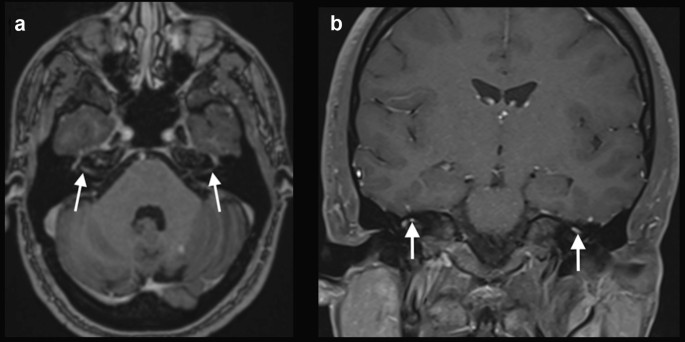

Case 5: A 65-year-old man with a history of osteoarthritis and atrial fibrillation presented with fever and generalized myalgia. A nasal swab was positive for SARS-CoV-2 during the first week of symptoms. After 2 weeks, he started having a headache and symptoms of left facial nerve palsy and lower limbs weakness. Neurologic examination revealed signs of bilateral facial nerve palsy, predominately in the left side, associated with lower limbs areflexia. A brain MRI was performed 1 week after the neurological symptoms onset, which showed bilateral gadolinium enhancement in the canalicular and labyrinthine portions of the facial nerves (Fig. 5). Lumbar spine MRI showed gadolinium enhancement in the cauda equina nerve roots. Electroneuromyography was suggestive of acute inflammatory demyelinating polyneuropathy, and CSF examination showed no cells, protein level: 100 mg/dl, compatible with Guillain-Barré syndrome. RT-PCR for SARS-CoV-2 in the CSF was negative. The patient received intravenous immunoglobulin, and presented partial improvement of the neurological symptoms.

Fig. 5

figure 5

COVID-19 associated with bilateral facial nerve palsy. Brain MRI showed bilateral gadolinium enhancement in the canalicular and labyrinthine portions of the facial nerves on axial T1-weighted spin-echo imaging (arrows in a) and coronal fat saturation T1-weighted spin-echo imaging (arrows in b)

Case 6: A 33-year-old previously healthy man presented with fever for one week, associated with a positive nasal swab for SARS-CoV-2. After 2 weeks, he started with bilateral facial nerve palsy. Brain MRI, performed 3 days after the neurological symptoms onset, demonstrated gadolinium enhancement in the canalicular and labyrinthine portions of the facial nerves (Fig. 6). The patient was also treated with oral prednisone, 60 mg/day, for 7 days, with complete recovery.